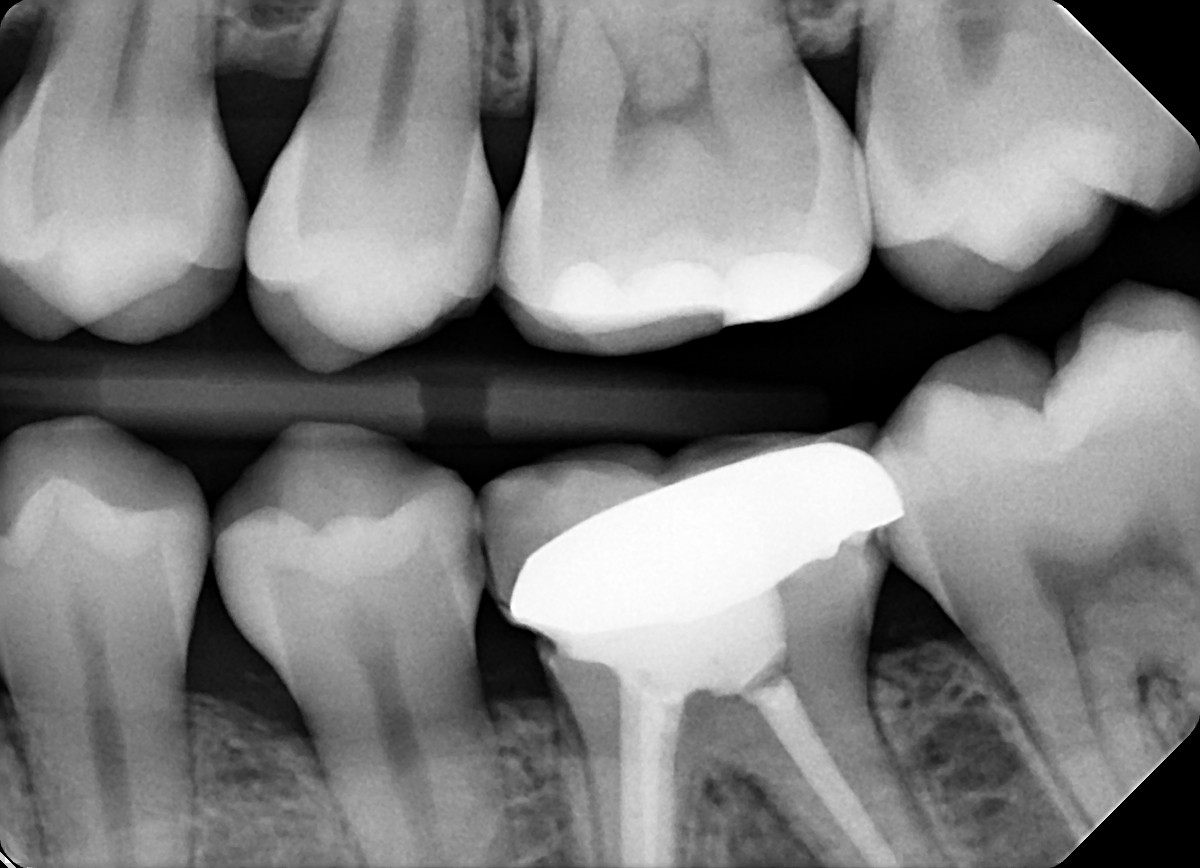

2. What option can be selected for the X ray bellow?